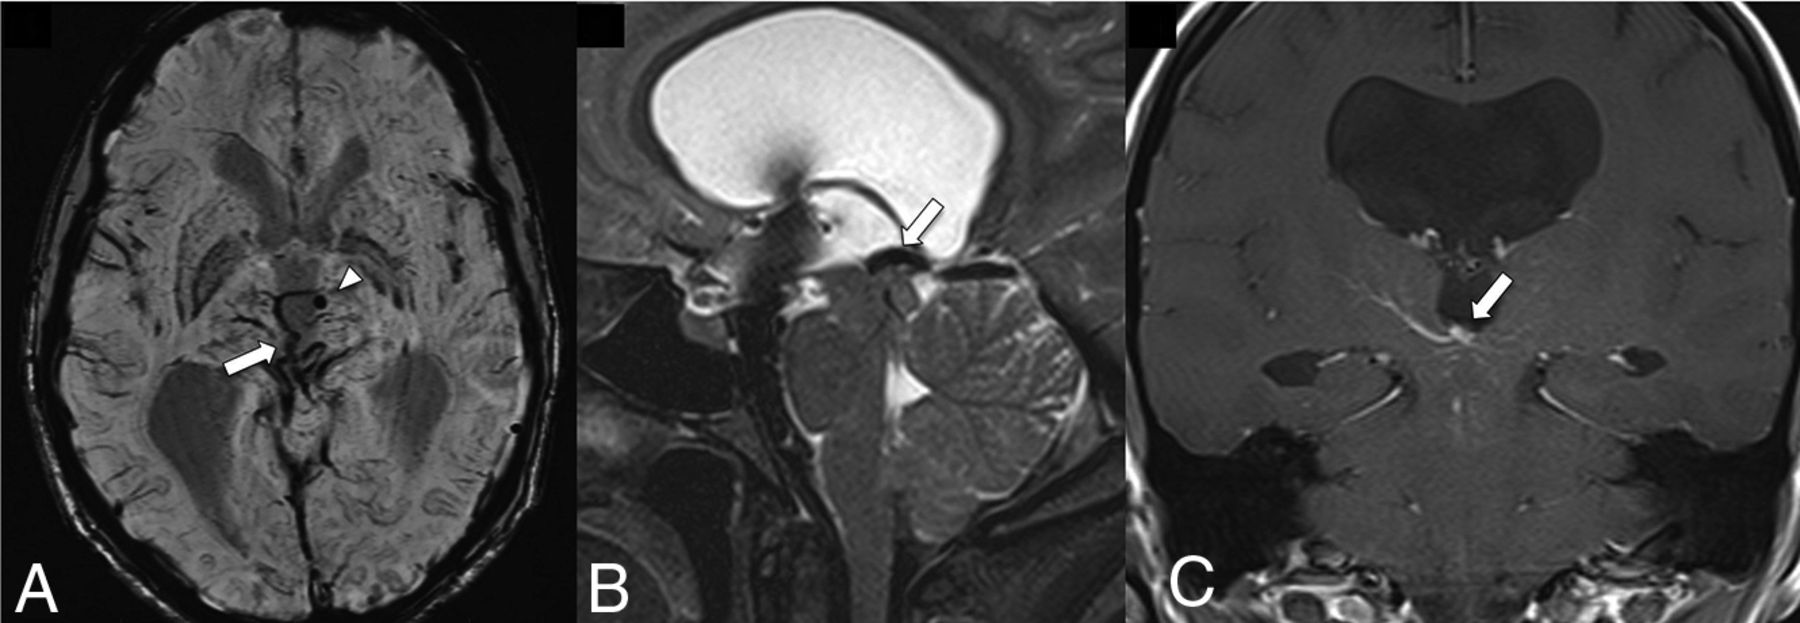

CCMs are vascular sinusoidal lesions lined by a single endothelial layer in a background of a collagenous matrix. CCMs are devoid of arterial or venous communication. They have a strong association with sporadic DVAs, with a frequency of coexistence of between 2% and 33% (Fig 1). The prevalence of CCMs with DVAs also have a positive correlation with increasing age.4 SWI is the ideal sequence to detect DVAs with CCMs due to the increased contrast conspicuity of the deoxyhemoglobin in the venous blood and the presence of blood products in CCMs. The SWI sequence on high-field-strength 7T MR imaging is more sensitive for depicting smaller-sized DVAs associated with sporadic CCMs, which may otherwise not be visible on 3T MR imaging.9

FLAIR (A) shows a mixed-signal-intensity CCM (arrowhead) in the left insular cortex with an internal blood-fluid level and no perilesional edema. A collector vein of a DVA (arrow) is seen from the ventricular ependyma to the CCM, which is barely visible on the SWI (B) and becomes more conspicuous on the susceptibility-weighted MIP image (C).